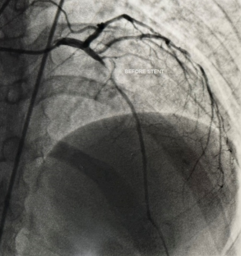

- During the procedure, a thin flexible tube (catheter) is inserted through an artery in the wrist or groin and guided to the heart. A colorless contrast dye is injected, allowing detailed X-ray images to show whether any coronary arteries are narrowed or blocked, and the exact location and severity of the blockage.

Angiogram showing detailed images of the coronary arteries and areas of narrowing.